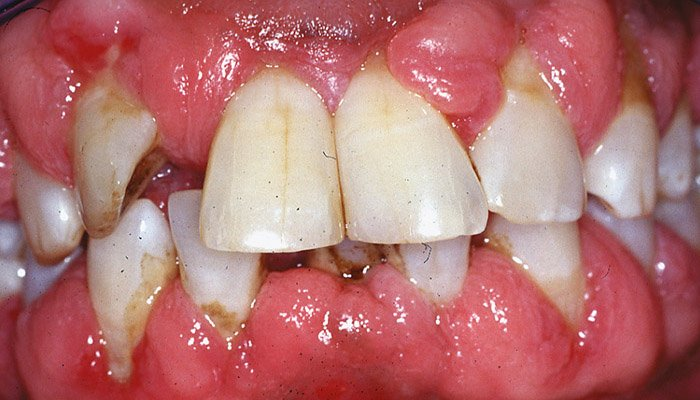

abnormalities of the oral mucosa - changes in colour - red , examples 5

(severity of) Periodontitis – Diabetes, Cardiovascular disease